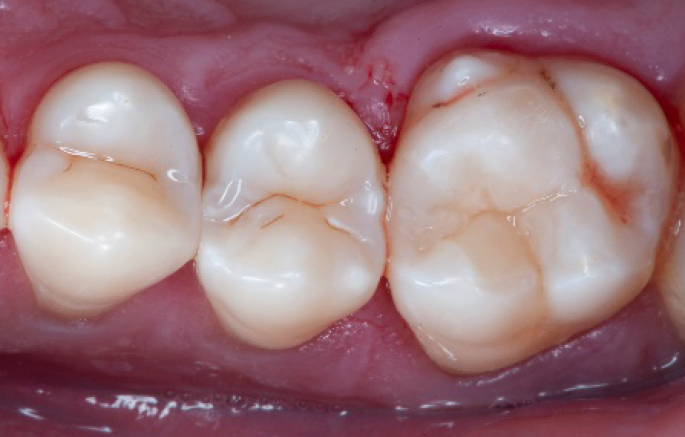

Step 11:

Occlusal surface restored using Spectra ST4 composite in shade A2.

Step 12:

The situation after rubber dam removal.

Step 13:

Occlusal check

Step 14:

2 weeks control

Final situation 2 weeks after the filling. Great comfort and no sensitivity at all were reported by the patient.